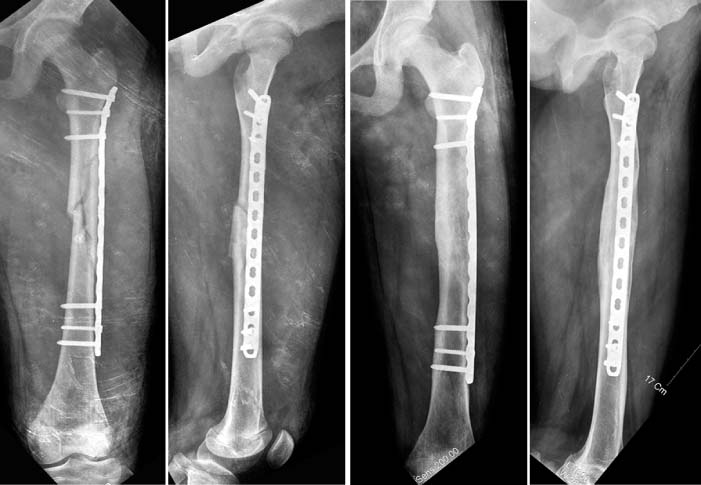

Fig. 1

A femoral shaft fracture with a butterfly fragment in 11 years-old girl.

Fig. 2

When flexible nails are remained too long distally, they will protrude the skin and soft tissue (arrow) and it provokes the infection and knee stiffness.

Fig. 3

Although the femoral fracture was well reduced by flexible nails (left), the nails were bent and varus deformity occurred because the patient had a weight-bearing too early (right).

jkfs-21-169-g003.jpg